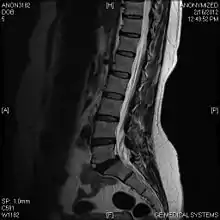

Limbus vertebra

A limbus vertebra is a bone tubercle formed by bone trauma on a vertebral body, bearing a radiographic similarity to a vertebral fracture. The anterior-superior corner of a single vertebra is the common site for this defect although it can also be seen at the inferior corner as well as the posterior or anterior margin. Anatomically, it is assumed to be an intra-vertebral body herniation of the disc material occurring during adolescent growth spurt when the ring apophysis has not yet fused. It was first described by Schmorl in 1927 and later in detail by Leif Sward and Adad Baranto.

Viewed in a lateral radiograph, it appears as a triangular shaped bone fragment, not unlike an anterior lip fracture, but with softer edges.

Limbus vertebra is not always symptomatic, but severe cases may lead to more serious pathological conditions and chronic pain. In rare instances, a posterior limbus vertebra has been described causing radiculopathy due to nerve root compression.